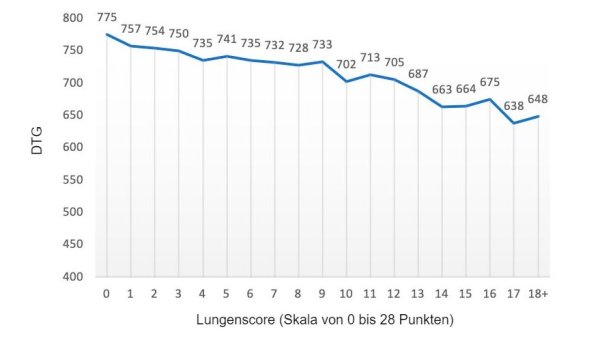

Wie wirkt sich eine Lungenentzündung auf die wirtschaftliche Leistung eines Betriebs aus? Welche Ähnlichkeiten gibt es zwischen Lungenentzündung und Hitzestress?